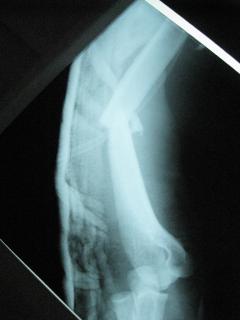

Περίπτωση 1ου ασθενούς

Τα εν λόγω κατάγματα είναι αρκετά συνηθισμένα και συχνά συμβαίνουν μετά από τροχαία ατυχήματα ή πτώση από ύψος. Παρατηρείται εξαιρετικά μεγάλη ποικιλία στη μορφή τους, κατα κανόνα όμως είναι σοβαρά και πολλές φορές ανοικτά – δηλ με τραύμα στο σημείο του κατάγματος – κάτι που αυξάνει τον κίνδυνο λοίμωξης και επιβαρύνει την πορεία της θεραπείας. Στα κατάγματα των άνω άκρων ενδέχεται να υπάρξει και τραυματισμός νεύρων, που χρειάζεται επίσης αντιμετώπιση.

Με τα σύγχρονα μέσα που διαθέτουμε, όλα σχεδόν αυτά τα κατάγματα πρέπει να αντιμετωπίζονται χειρουργικώς. Υπάρχει πληθώρα υλικών οστεοσύνθεσης (πλάκες διαφόρων τύπων, ενδομυελικοί ήλοι, συστήματα εξωτερικής οστεοσύνθεσης) που είναι διαθέσιμα και επαφίεται στην εμπειρία του χειρουργού η επιλογή.

Όλες οι φωτογραφίες ολες προέρχονται από το προσωπικό αρχείο του κου Μ. Τυλλιανάκη